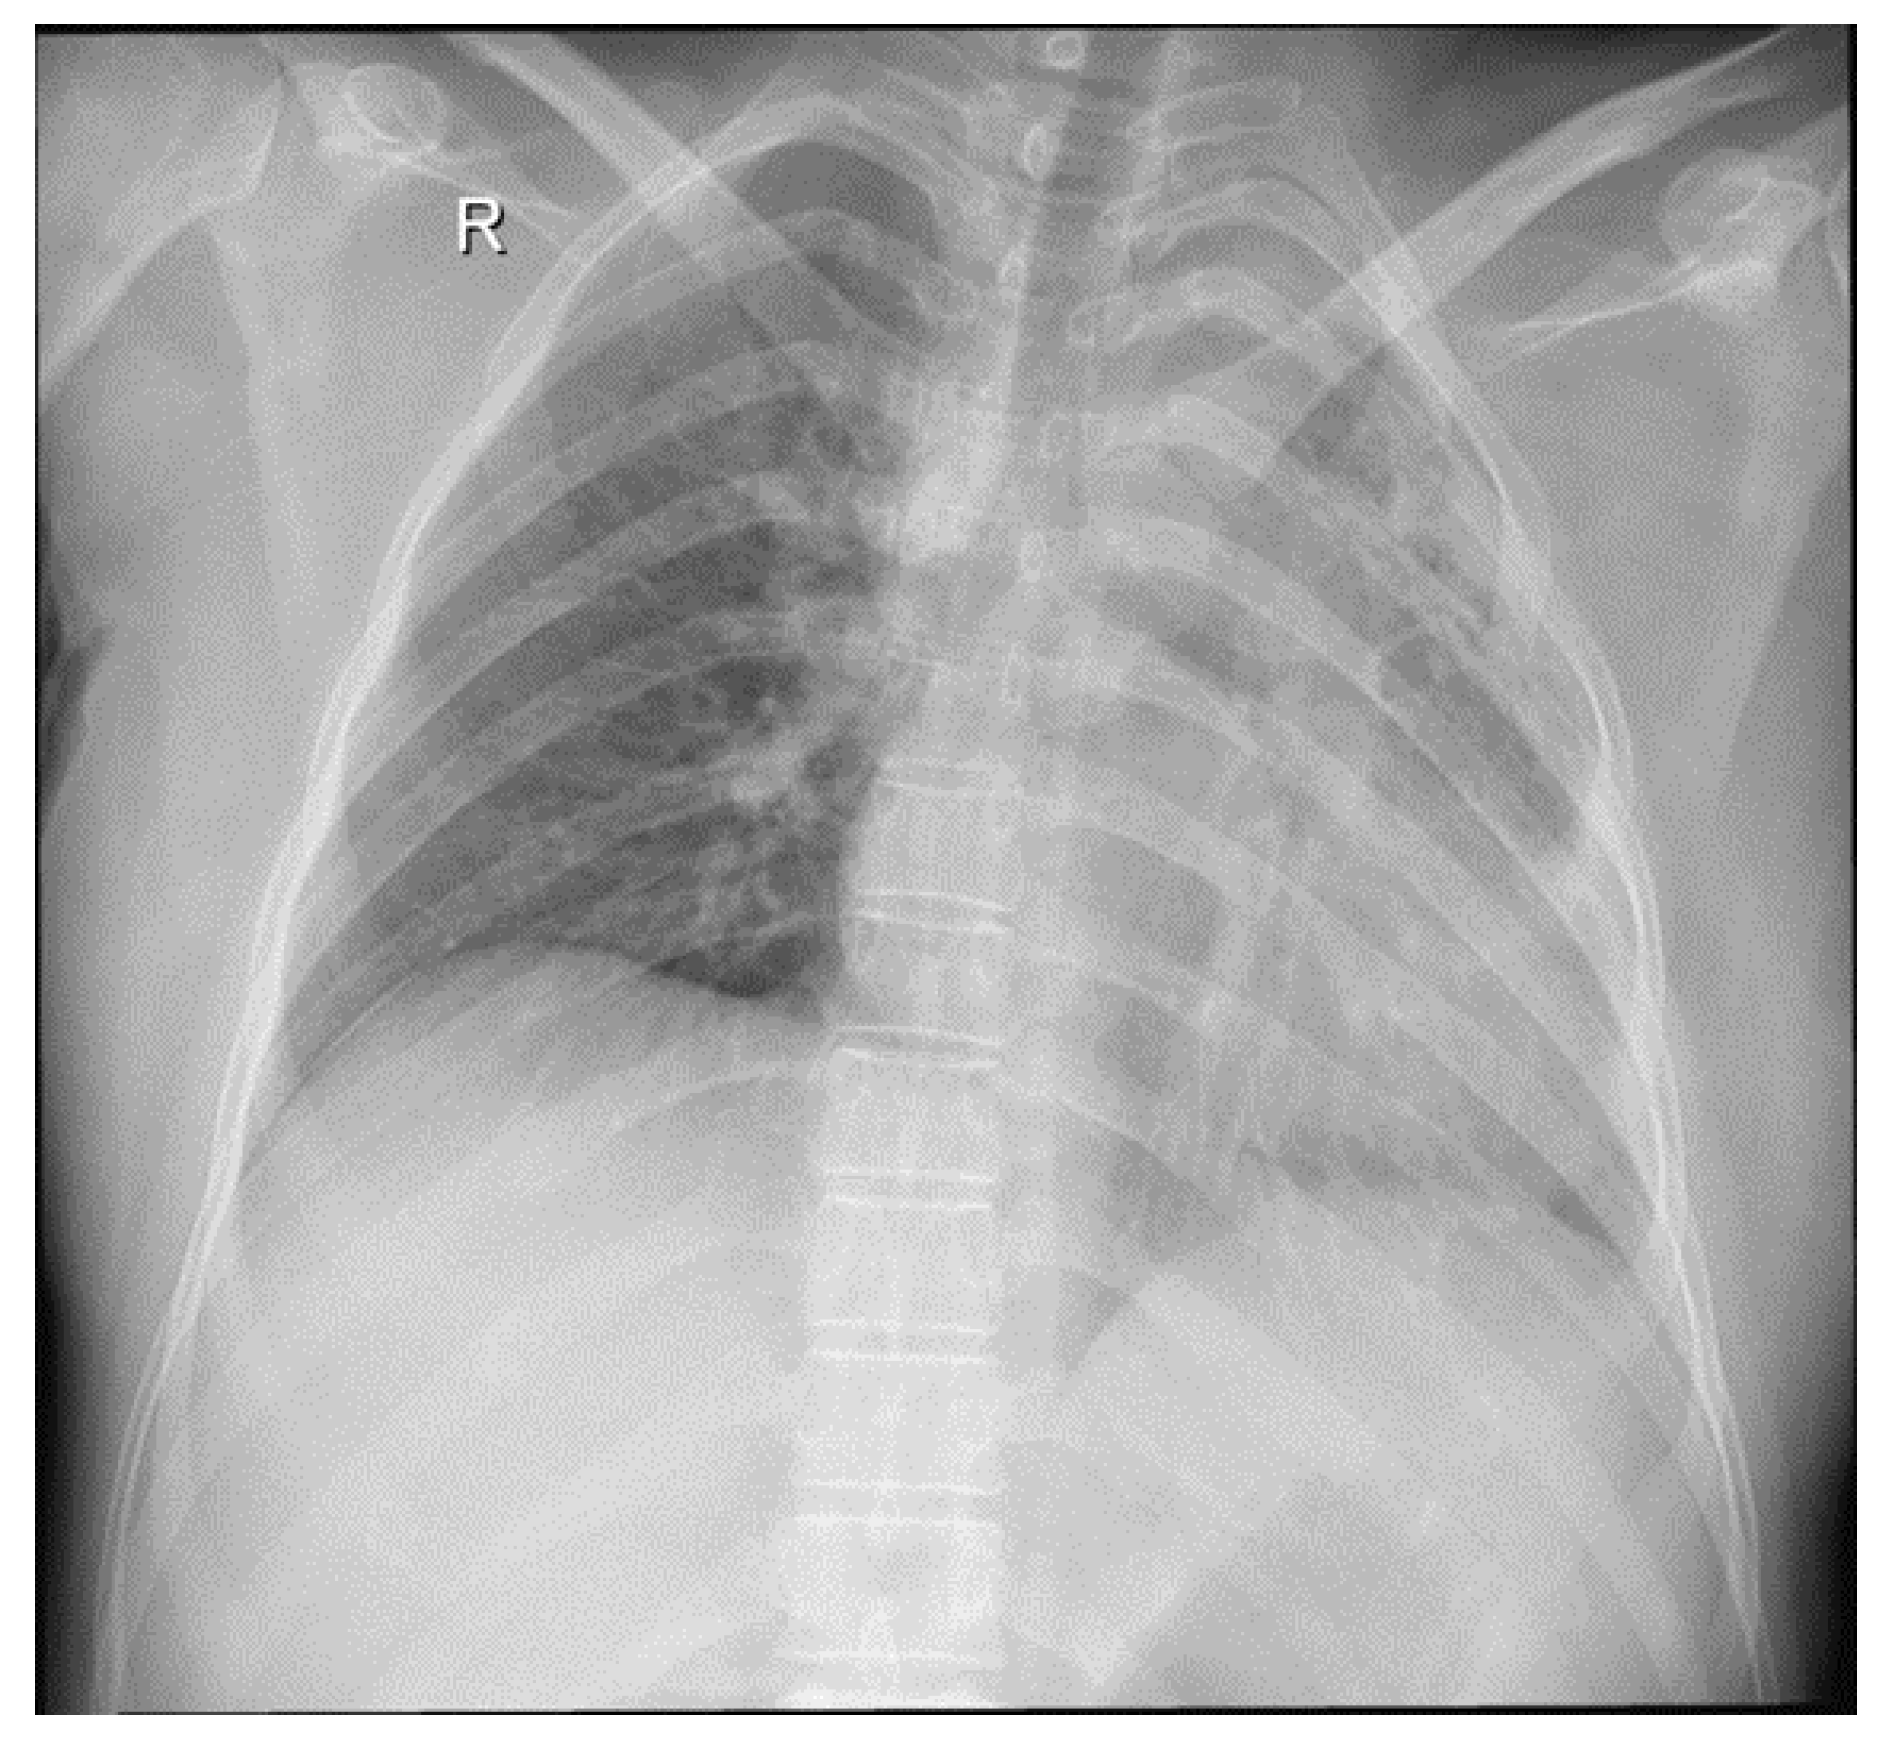

- Radiological evidence of chronic pulmonary lesion;